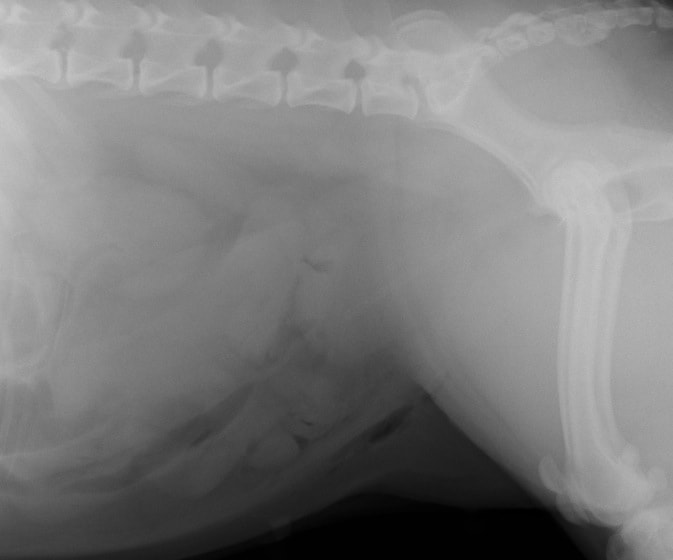

術前レントゲン

腹部臓器が胸腔内に脱出し、腹部と胸部の境界および心臓や肺の陰影が不明瞭になっています。また、胸腔内に消化管のガス陰影が認められます。